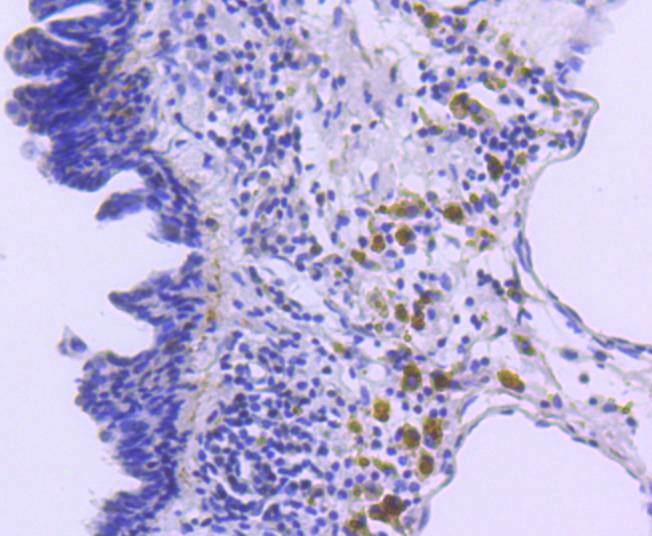

Immunohistochemical analysis of paraffin-embedded mouse lung tissue using anti-p27 KIP 1 antibody. The section was pre-treated using heat mediated antigen retrieval with sodium citrate buffer (pH 6.0) (high pressure) for 2 minutes. The tissues were blocked in 5% BSA for 30 minutes at room temperature, washed with ddH2O and PBS, and then probed with the primary antibody (HA750157, 1/50) for 30 minutes at room temperature. The detection was performed using an HRP conjugated compact polymer system. DAB was used as the chromogen. Tissues were counterstained with hematoxylin and mounted with DPX.